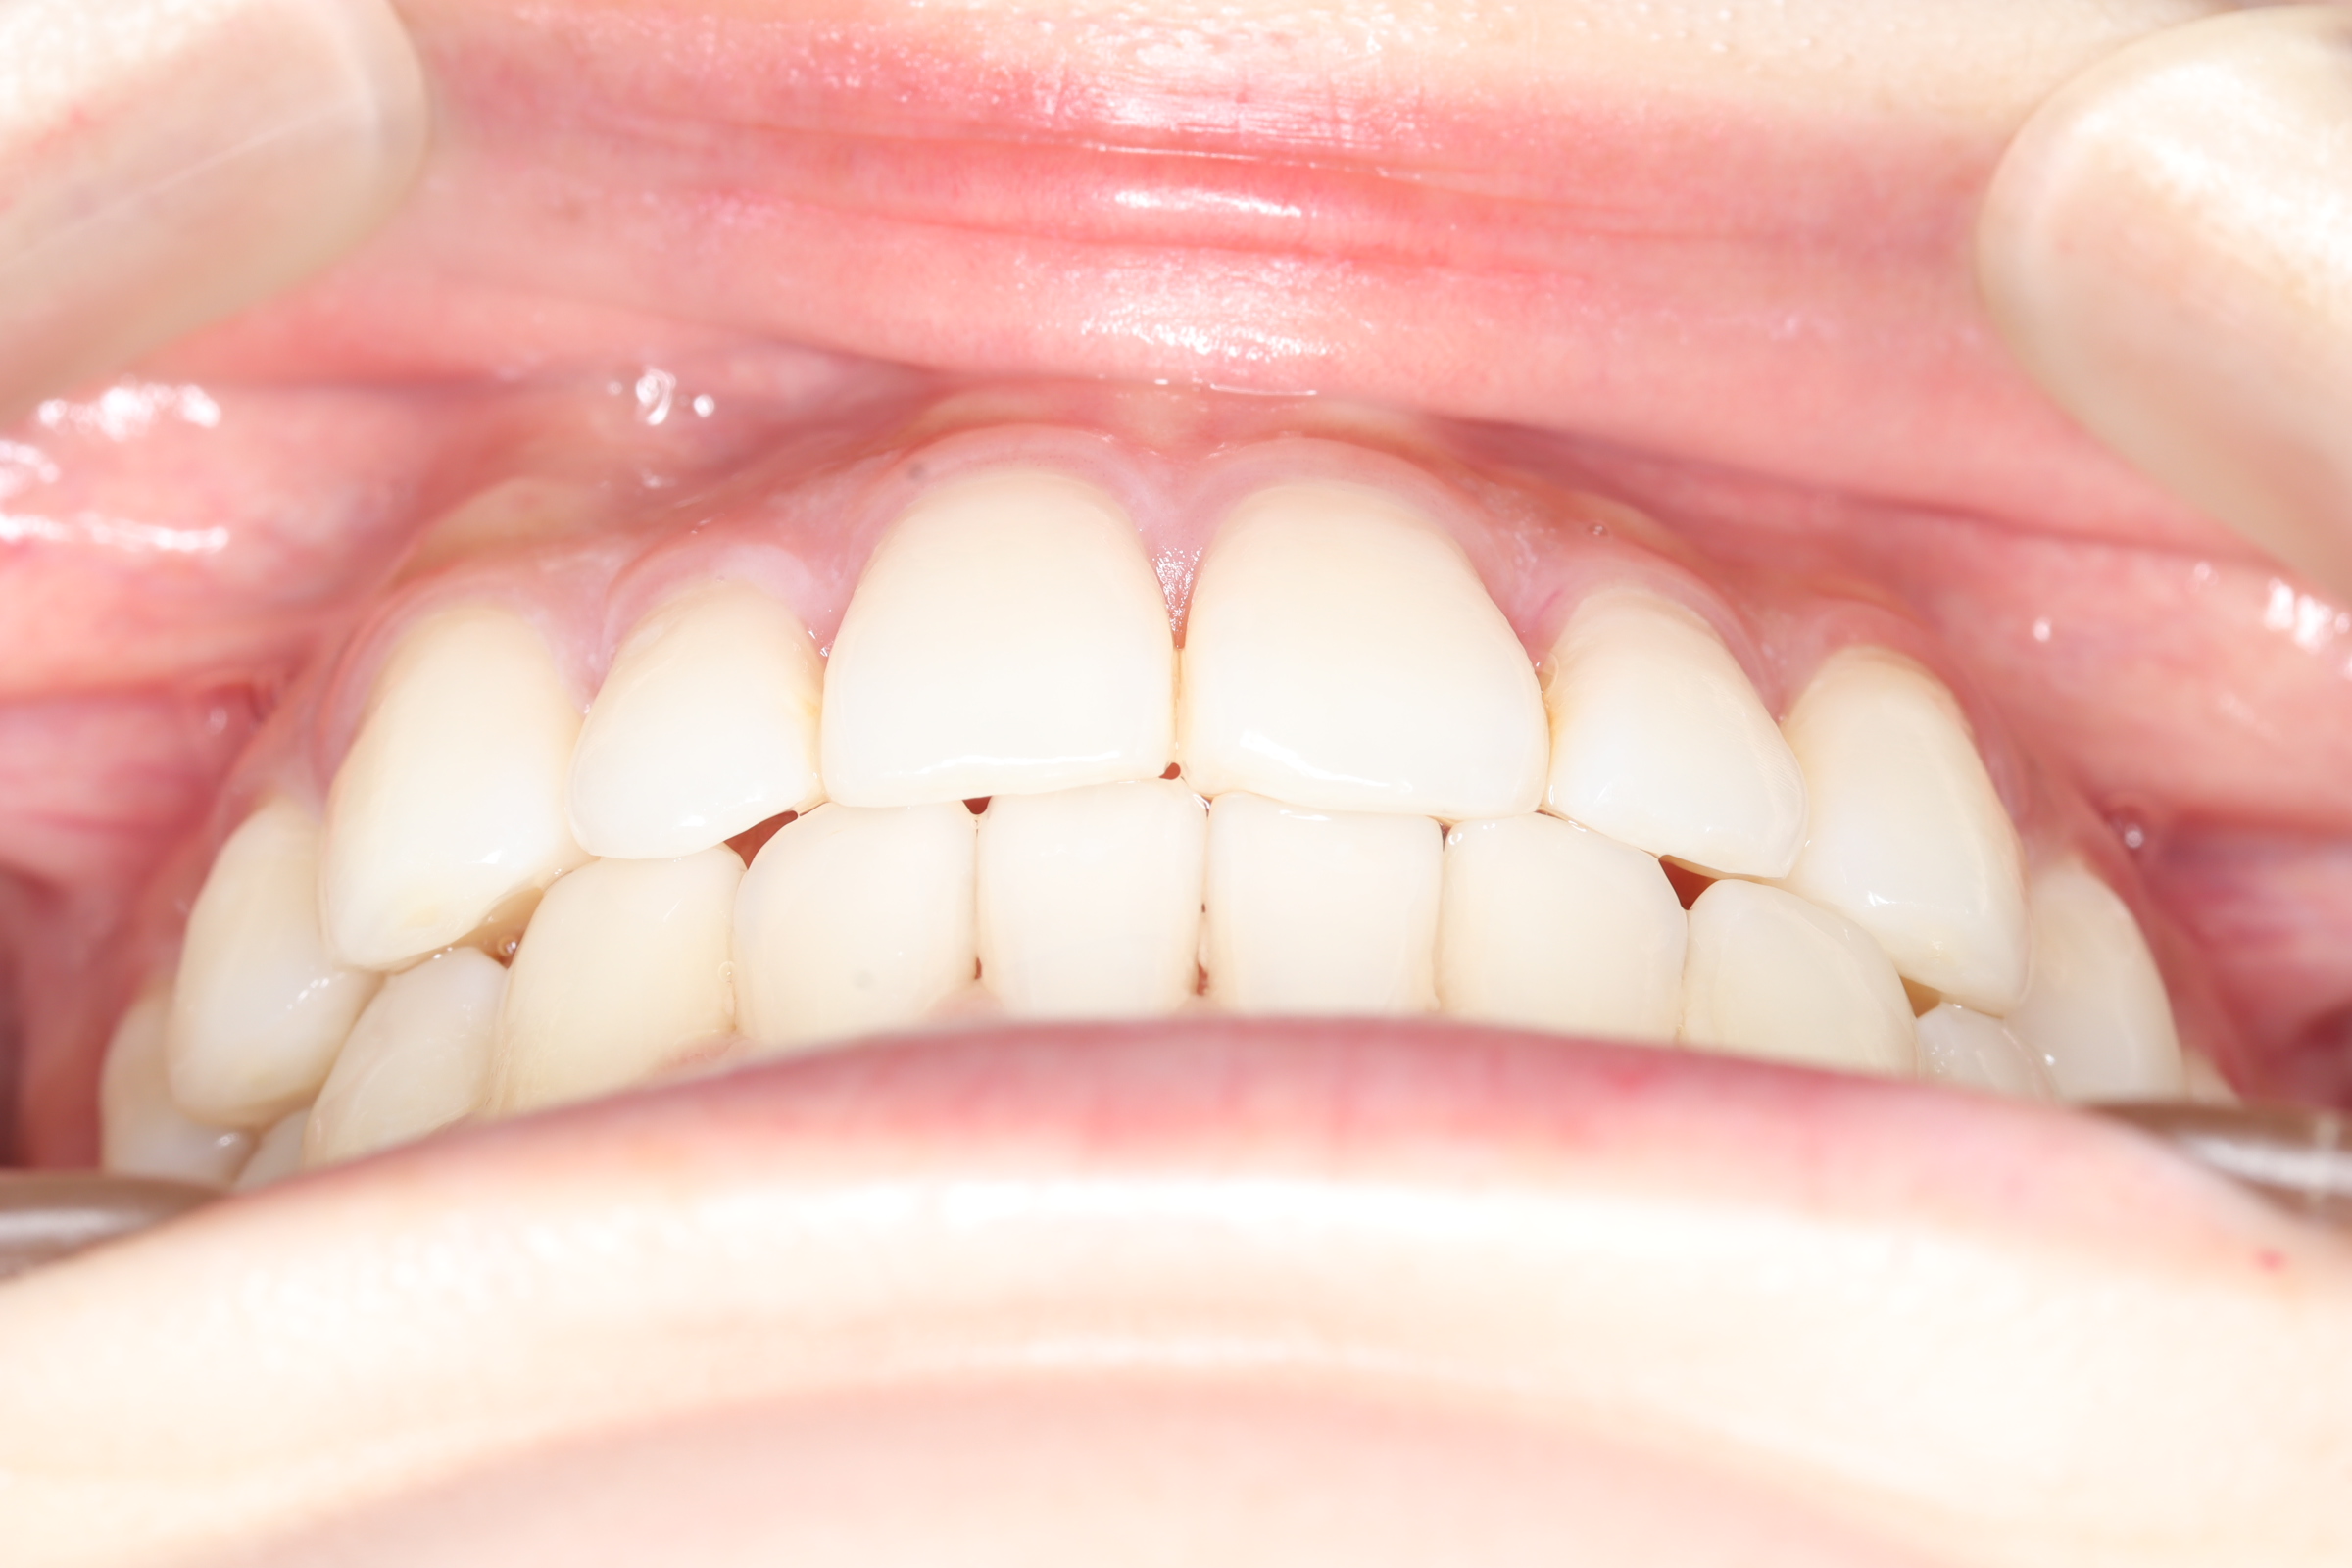

口腔内の変化

![]() | ![]() | ![]() |

| ↓ | ↓ | ↓ |

| 治療前 | 骨格的には受け口の患者さんですが、上顎前歯の唇側傾斜が大きく、患者さんとしては出っ歯だと思われていたパターンです。 元々口元の突出感はほとんどなかったため、歯を抜かずに上下顎ともに歯列を後方に移動させることにより主訴を改善させることとしました。 |

| 治療後 | 前歯から奥歯まで全体的に緊密な咬み合わせになっています。 治療前後のセファログラムのトレースの重ね合わせを比較すると、上下の歯列の後方移動ができ、それにより口元もよりすっきりしました。 また前歯の唇側傾斜も改善されています。 |